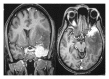

Inflammatory pseudotumor most commonly occurs in the orbit and produces orbital pseudotumor, but extension into brain parenchyma is uncommon. We report a case of inflammatory pseudotumor involving sphenoid sinus, cavernous sinus, superior orbital fissure, orbital muscle, and intracranial extension into left temporal lobe producing right hemiparesis and wernicke's aphasia. The patient improved clinically and radiologically with steroid administration. This paper provides an insight into the spectrum of involvement of inflammatory pseudotumor and the importance of early diagnosis of the benign condition.